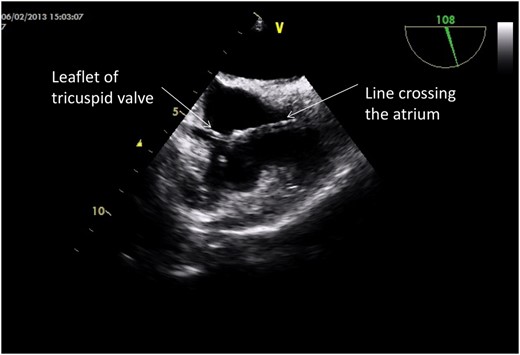

Under general anaesthesia, a cut down was performed onto the left internal jugular vein at the entry point of the catheter. The fibrin sheath was incised and traction on the catheter failed to release it. Simultaneous traction and snaring of the catheter tip via a femoral venous approach was failed. A hydrophilic guide-wire was passed through the catheter and out of a side hole of the line, which was then snared in the right atrium. Synchronous traction was applied to both ends of the line via the snare and the external portion of the line, but the line could not be freed. Balloon angioplasty within the lumen of the line was performed in order to attempt splitting of the surrounding fibrin sheath. Furthermore, upon traction of the external portion of the line, the unusual finding of a palpable transmitted pulse via the catheter was noted. In order to investigate this further, a trans-oesophageal echocardiogram was performed intra-operatively. This showed the proximal portion of the line passing through the tricuspid valve, with its tip adherent to one of the valve leaflets (Fig. 2). At this stage, the external part of the catheter was excised and the catheter remnant internalized with a plan for subsequent removal via open-heart surgery.

Trans-oesophageal echocardiogram with bicaval view showing the position of the line in relation to the tricuspid valve.